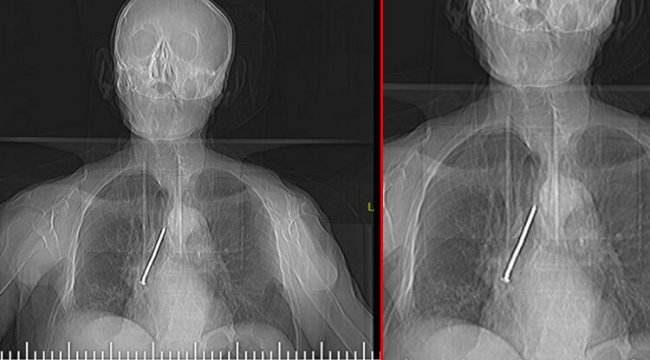

Elazığ'da öksürük ve nefes darlığı şikayetiyle hastaneye başvuran Keko Ateş'in (91) nefes borusunda 10 santimlik çivi tespit edildi.